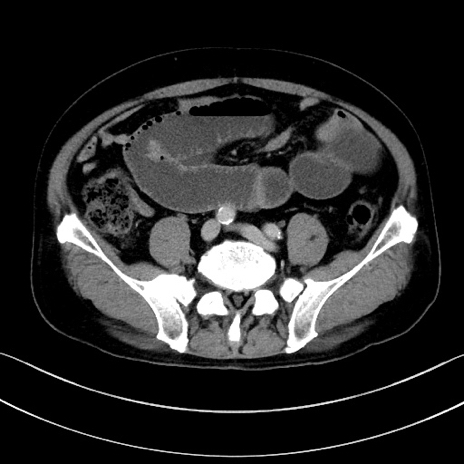

症例15(横断像)

【症例】70歳代男性

【主訴】腹痛

【現病歴】今朝から腹痛あり。全体的に痛い。特に左上の方。排ガスが今日はない。冷や汗が出る。

【既往歴】直腸癌術後

【身体所見】左側腹部〜上腹部に圧痛あり。腹膜刺激症状明らかなではない。軽度反跳痛。左下腹部に術後瘢痕あり。

【データ】WBC 7700、CRP 0.02